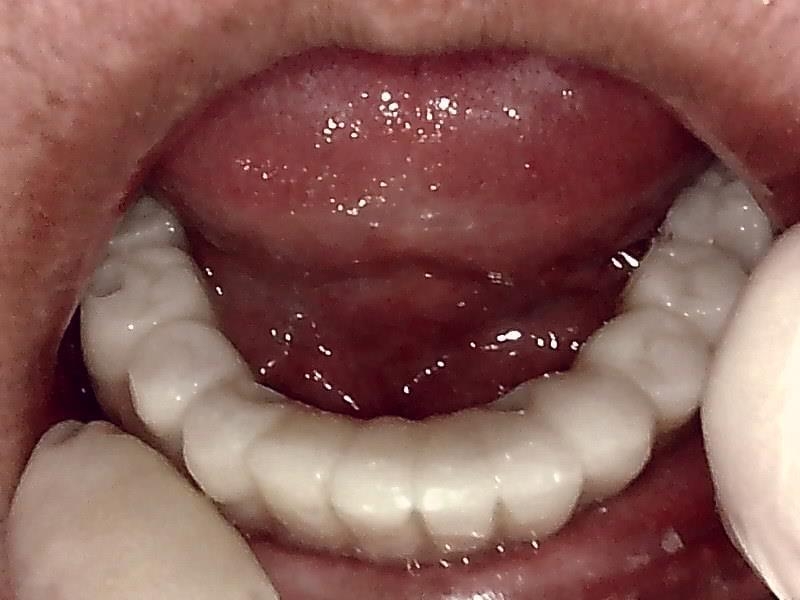

上部構造装着した状態です。

下顎のインプラント装着した、上顎総義歯との被蓋関係

完成後、予後経過はとても良好な状態です。